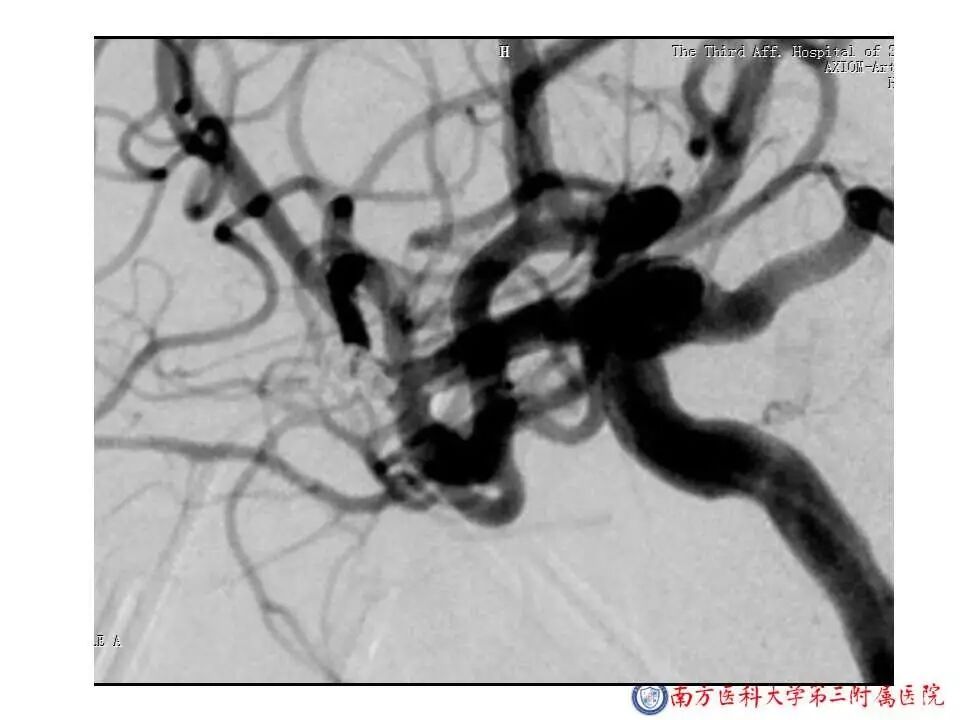

今天为大家分享的是“强生医疗CNV-神经介入专栏”第二十五期,由南方医科大学第三附属医院神经外科主任黄理金教授带来的“Enterprise支架辅助栓塞动脉瘤的优势”精彩讲课视频及PPT,欢迎观看。文章仅代表作者个人观点,如有不同见解,欢迎同道斧正!